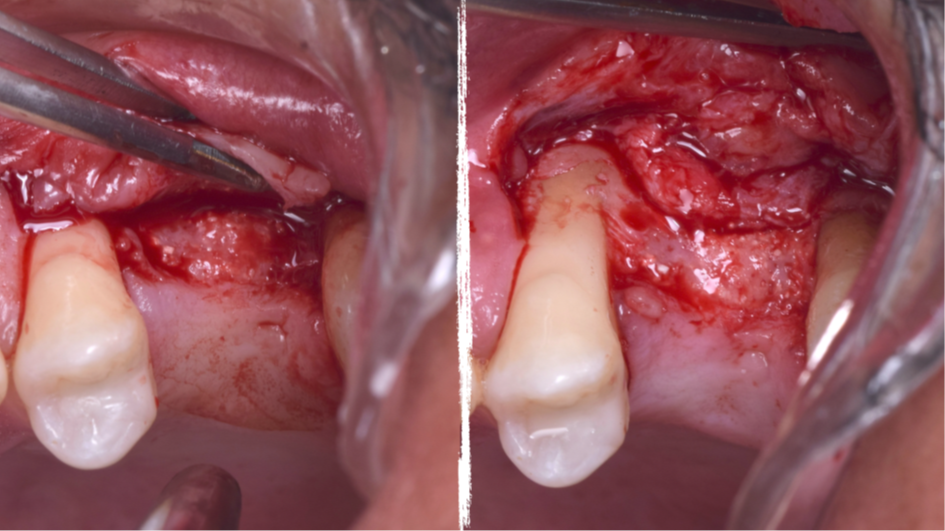

O presente trabalho tem como objetivo fazer um relato de caso clínico de reintervenção em enxerto ósseo para levantamento de seio maxilar pela técnica da janela lateral com instalação simultânea de implante Maestro Superiore.